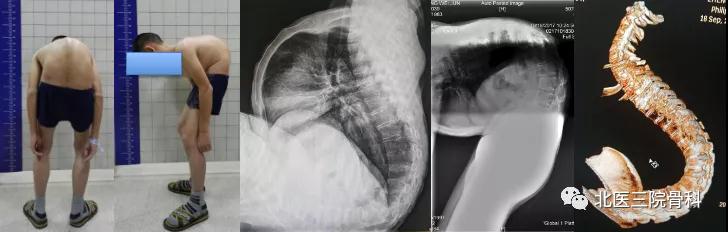

病例一

强直性脊柱炎后凸畸形大体照及影像学(术前)

强直性脊柱炎后凸畸形大体照及影像学

(术后)